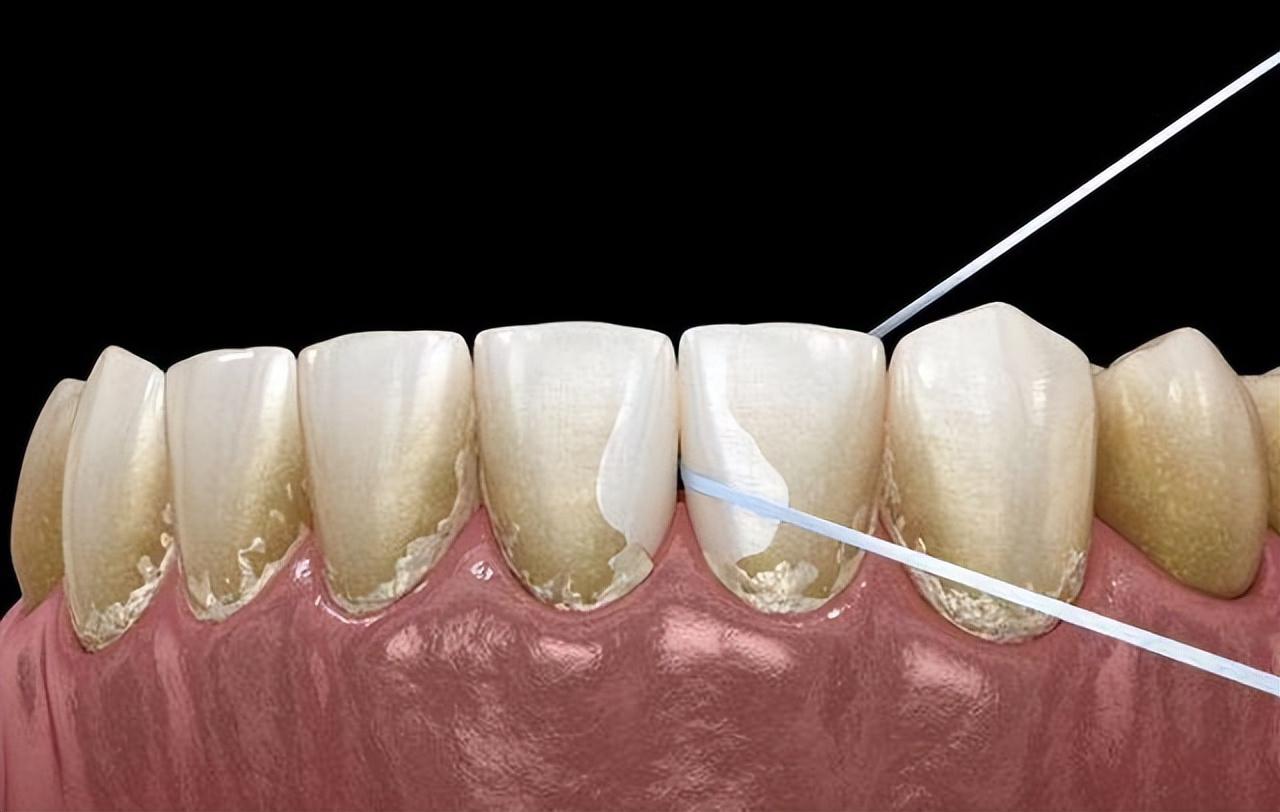

如果直接用手抠牙结石并不会将全部牙结石清除,因为牙结石不仅附着在牙龈内,同时还存在于牙根牙颈部和牙冠上,用手抠掉的牙结石,仅仅是附着在牙冠表面上,存在的其他部位的牙结石是无法用手指抠掉的。

用手指抠掉牙结石还容易造成牙龈损伤,因为指甲是非常锋利的,牙龈在多年牙结石伤害下已经非常脆弱和敏感,稍有不慎就会造成牙龈损伤,出血是小事感染就会严重损害口腔健康。

有些人也会用比较锋利的小器械抠掉牙结石,这样的做法更是大错特错,简直就是拿自己牙齿健康开玩笑,最终很可能会导致牙齿表面的牙釉质受到伤害。